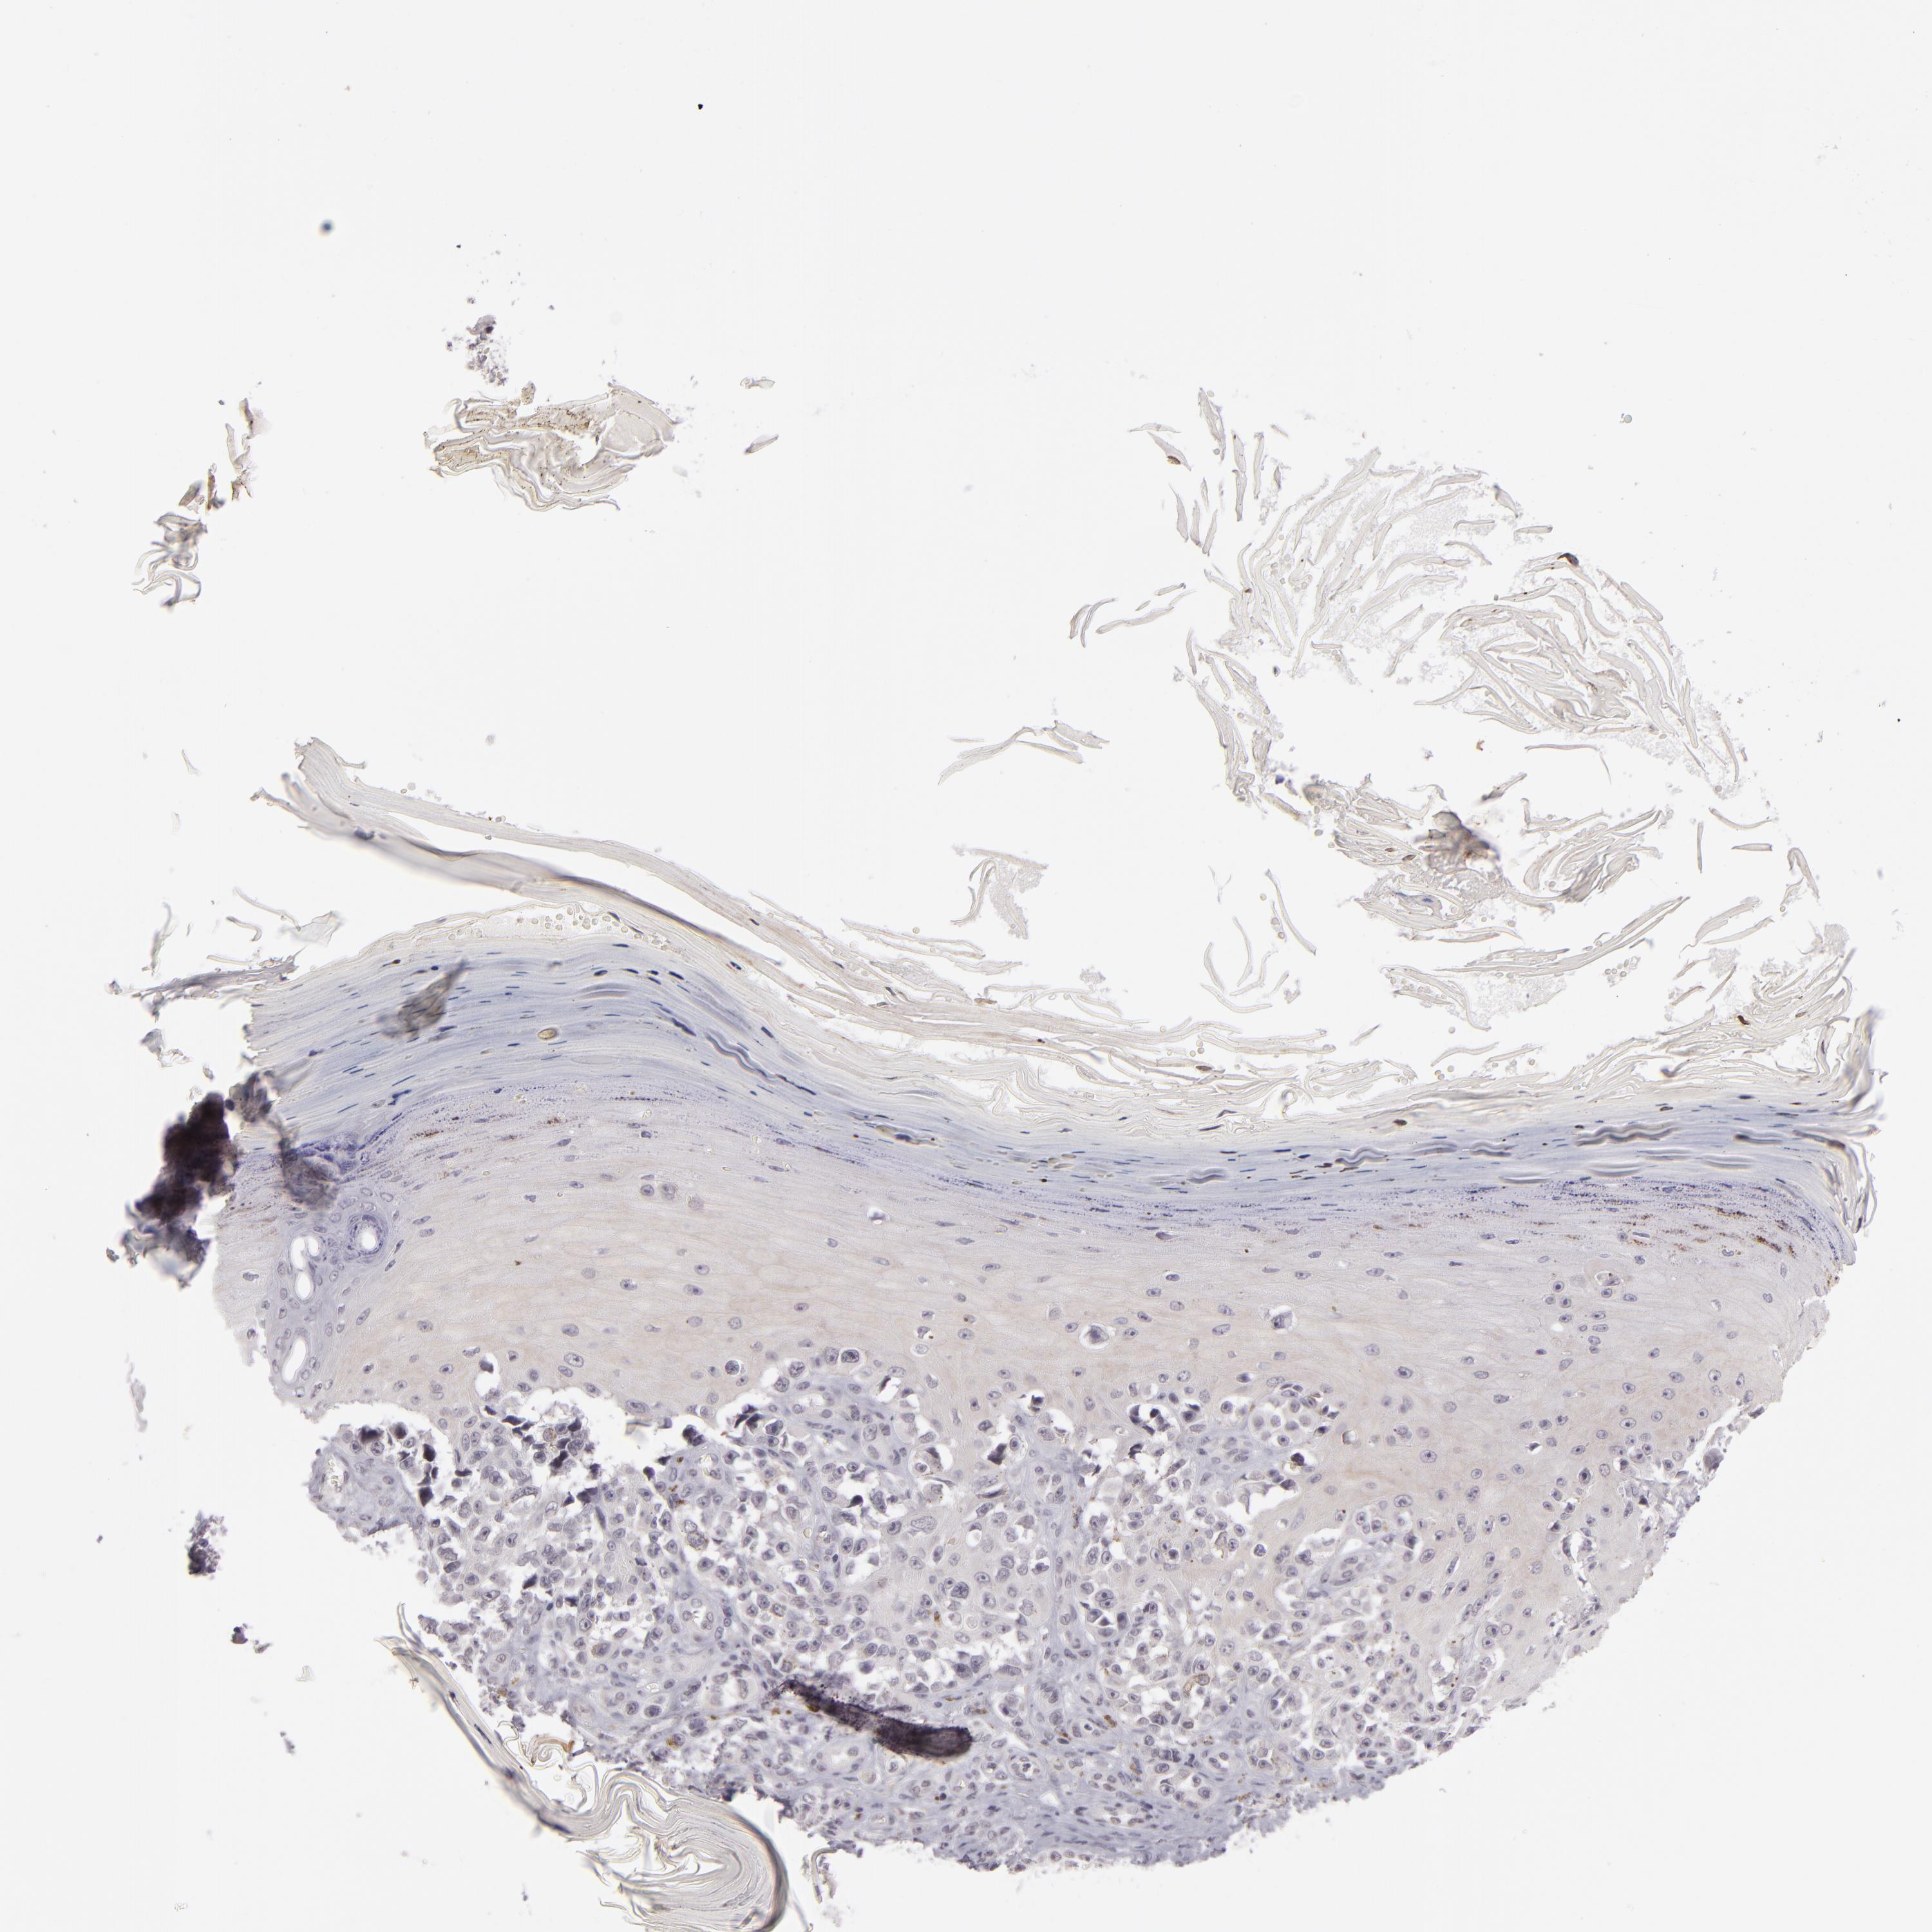

MELANOMA - Protein expressioni

A mouse-over function shows sample information and annotation data. Click on an image to view it in a full screen mode. Samples can be filtered based on level of antibody staining by selecting one or several of the following categories: high, medium, low and not detected. The assay and annotation is described here.

Note that samples used for immunohistochemistry by the Human Protein Atlas do not correspond to samples in the TCGA dataset.

Antibody stainingi

Antibody staining in the annotated cell types in the current human tissue is reported as not detected, low, medium, or high, based on conventional immunohistochemistry profiling in selected tissues. This score is based on the combination of the staining intensity and fraction of stained cells.

Each image is clickable and will lead to virtual microscopy that enables deeper exploration of all samples and also displays staining intensity scores, fraction scores and subcellular localization as well as patient and tissue information for each sample.

Antibody HPA001791

Staining

High

Medium

Low

Not detected

Intensity

Strong

Moderate

Weak

Negative

Quantity

>75%

75%-25%

<25%

None

Location

Nuclear

Cytoplasmic/membranous

Cytoplasmic/membranous,nuclear

Malignant melanoma, NOS